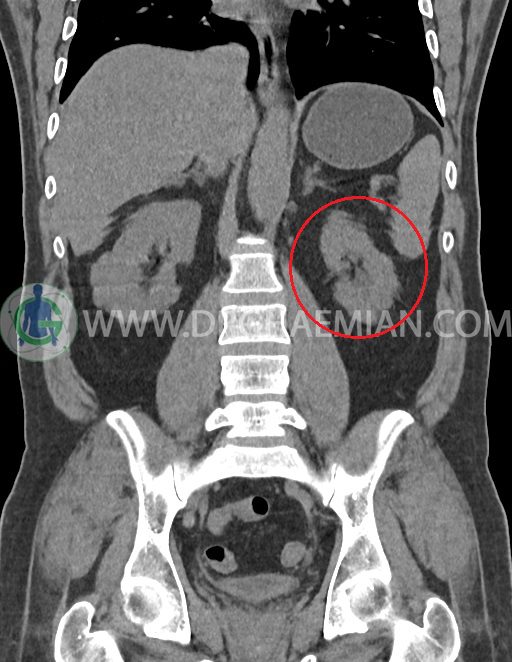

ام آر آی آتروفی عضلانی کتف بیمار

ام ار آی کتف یک روش تصویربرداری است که به وسیله آهنرباهای قدرتمند از قسمت کتف تصاویری ایجاد می کند. این نوع تصویربرداری از تشعشعات استفاده نمی کند. در این کیس آتروفی عضلانی کتف به همراه پارگی تاندون بالاخاری، بورسیت ساب دلتوئید و افیوژن مفصل دیده می شود.

– Complete tearing of supraspinatus tendon with grade 2 retraction and muscle atrophy

– AC joint hypertrophy with subacromial – subdeltoid bursitis

– Glenohumeral joint effusion

are seen.